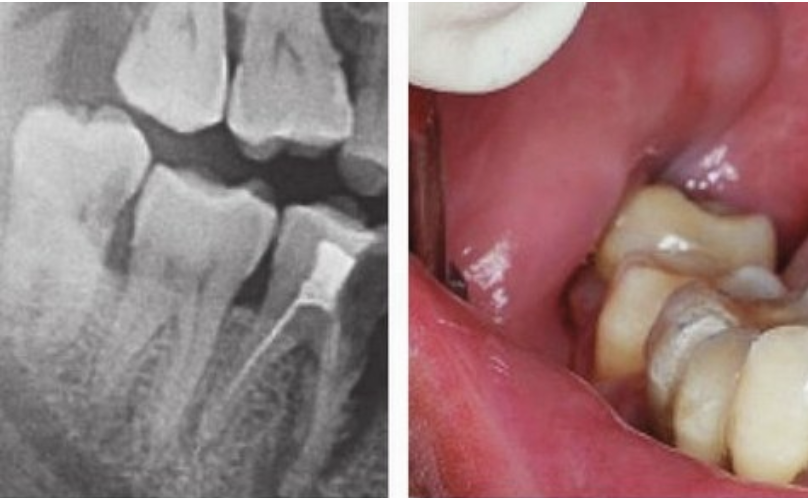

二、拔牙前為什么要先拍片子?因為就算同樣是拔智齒,每個人的牙齒情況也不盡相同。

拔牙前拍 X光片可以讓醫(yī)生看到肉眼看不到的牙根形態(tài)、生長狀態(tài)。

根據(jù) X光片的結(jié)果,醫(yī)生可以更地評估拔牙的難度,定制拔牙的方案,向患者更好地解釋一些可能存在的風險。

此外,有時候X光片還能發(fā)現(xiàn)肉眼看不見的斷在牙槽骨里的殘根,在手術(shù)時可以對拔除殘根更加地有把握。

(術(shù)前進行拍片,確定牙齒情況)